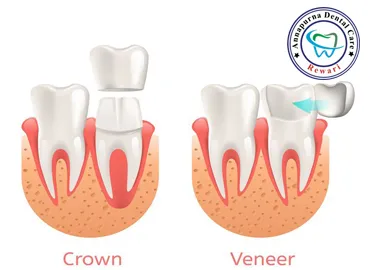

VENEERS & CROWNS

Both veneers and crowns can improve your smile and the function of your teeth.

Read More